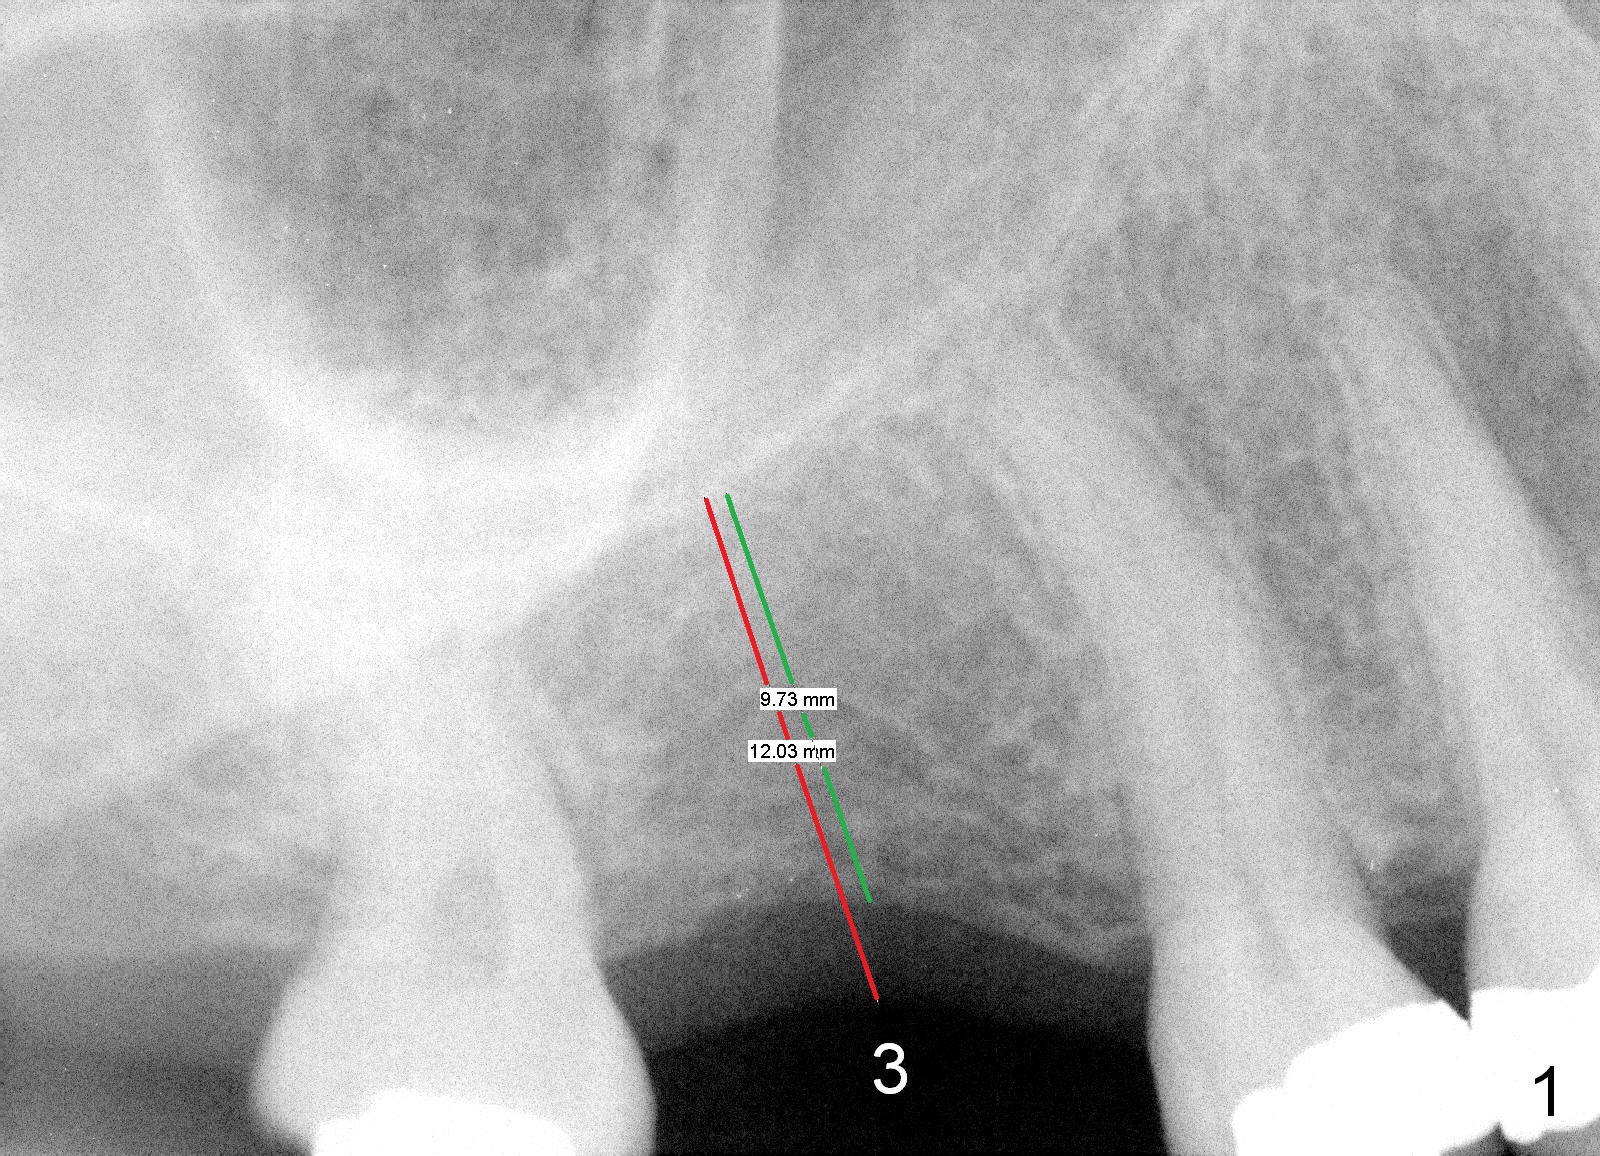

A 50-year-old lady requests implant placement at the site of #3 first. The ridge is mild to moderate atrophy. Immediately preop PA shows bone height ~ 10 mm (Fig.1 green line) and gingiva to sinus floor distance 12 mm (red line). A 10 mm incision is made over the crest. The bone is felt D3, whereas the earlier case D4. Bone expansion and condensation is still performed because it is the least invasive, no drill or suture. In brief the osteotomy is created by osteotomes, followed by taps (4.5-6 mm) (Fig.2: 4.5 mm). A 6x14 mm gingiva-level implant is placed with insertion torque of 60 Ncm (Fig.3 I). A 5x3 mm abutment (A) is placed for an immediate provisional. There is no bone resorption less than 4 months postop (Fig.4). After reprep, impression is taken for final restoration.